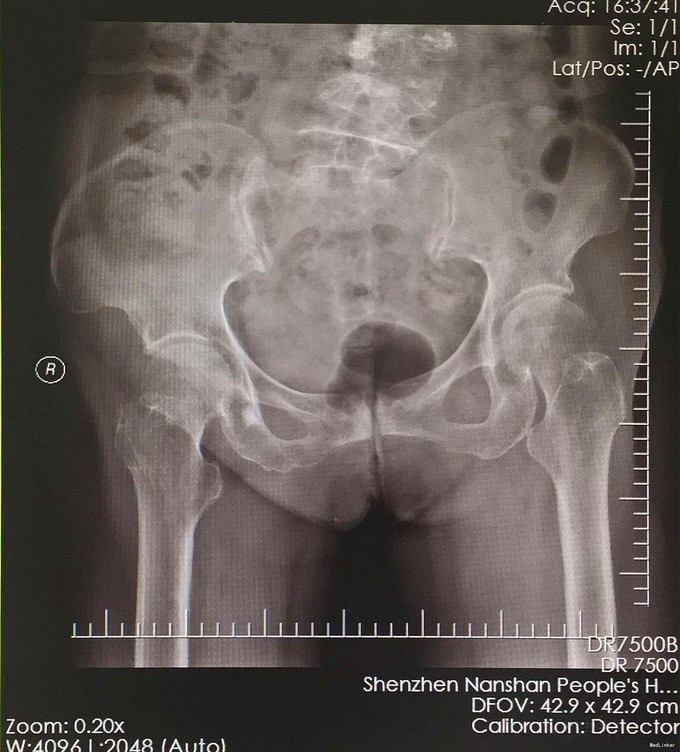

老年女性患者,因“右髋部跌伤疼痛、活动困难8小时”入院。 缘患者于8小时前走路无意中摔倒致右髋部受伤,当时感觉疼痛,无法站立,伤后由家属送入我院急诊,给予检查X光片显示“右股颈骨折”,急诊未做特殊处理,为进一步救治,收入我科。

体温37.1℃ 脉搏:79次/分 R:20次/分 舒张压:119mmHg 收缩压:86mmHg。 神清合作,应答切题、全身皮肤黏膜无黄染、浅表淋巴结无肿大,头颅五官无畸形,双侧瞳孔等大等圆,对光反射灵敏。颈软,胸廓对称,双肺呼吸清音,无干湿性罗音。心率79次/分,律齐有力,各瓣膜区无病理性杂音。腹部无异常体征,脊柱盆腔无畸形,双上肢及右下肢检查感觉及活动正常,左下肢检查见专科情况,肛门、外生殖器未检,各生理性反射存在,病理性反射未引出。 专科情况:右髋部无明显肿胀,右下肢呈屈髋、缩短、外形畸形,右髋关节周围广泛压痛,大转子叩击痛,右下肢长度稍短,右大转子在Nelaton线之上,右髋、膝关节活动受限,双下肢无水肿,末梢血运及感觉正常。 辅助检查:我院急诊骨盆正位片: 1、右骨大节骨折可疑,建议进一步检查。 2、右坐骨骨岛:双髋关节螺旋CT平扫+三维重建: a、右股颈骨骨折 b、考虑右髋臼下方髋骨内骨岛。

诊断:右股骨颈骨折 治疗:全髋关节置换术